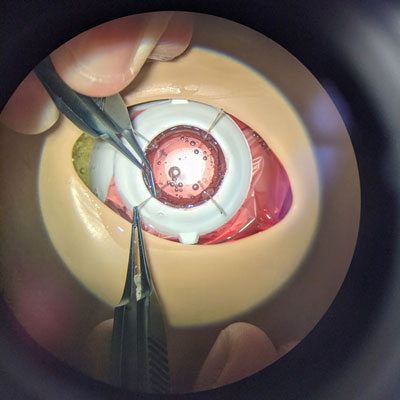

In this YES Connect column, two surgeons described their techniques for how and when to successfully fixate a secondary lens when the capsule is either not present or not secure enough for traditional IOL implantation.